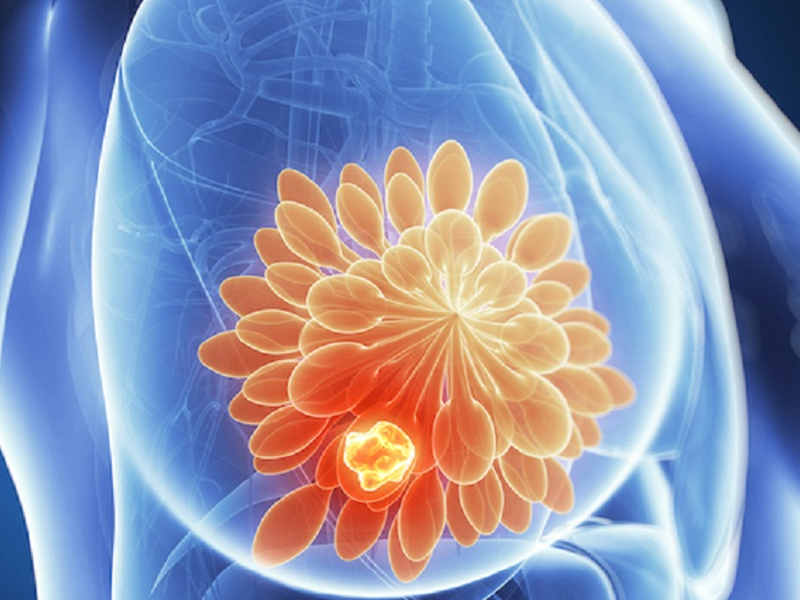

瀏覽:804 港大研究:脂肪肝加速乳腺癌惡化 |